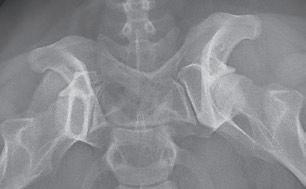

Displasia de cadera (I): etiopatogenia, signos clínicos y pruebas diagnósticas 26